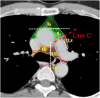

The purpose of this study was to develop a consensus-based computed tomographic (CT) atlas that defines lymph node stations in radiotherapy for lung cancer based on the lymph node map of the International Association for the Study of Lung Cancer (IASLC). A project group in the Japanese Radiation Oncology Study Group (JROSG) initially prepared a draft of the atlas in which lymph node Stations 1-11 were illustrated on axial CT images. Subsequently, a joint committee of the Japan Lung Cancer Society (JLCS) and the Japanese Society for Radiation Oncology (JASTRO) was formulated to revise this draft. The committee consisted of four radiation oncologists, four thoracic surgeons and three thoracic radiologists. The draft prepared by the JROSG project group was intensively reviewed and discussed at four meetings of the committee over several months. Finally, we proposed definitions for the regional lymph node stations and the consensus-based CT atlas. This atlas was approved by the Board of Directors of JLCS and JASTRO. This resulted in the first official CT atlas for defining regional lymph node stations in radiotherapy for lung cancer authorized by the JLCS and JASTRO. In conclusion, the JLCS-JASTRO consensus-based CT atlas, which conforms to the IASLC lymph node map, was established.